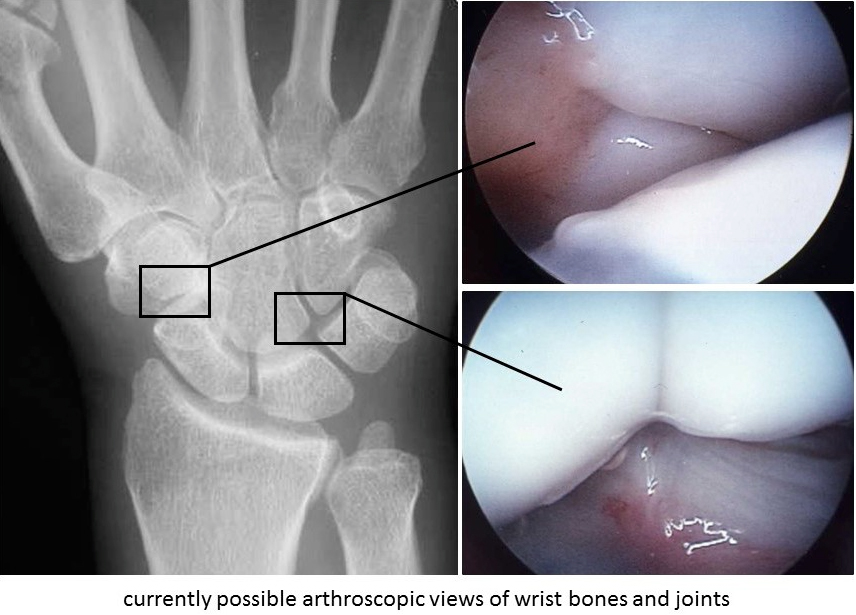

Current techniques and instruments even allow the surgeon to place and tie

sutures inside a joint. Such minimally invasive surgery allows for faster and

more complete rehabilitation. Because the knee joint is large, the innovations

started there, but now orthopedists also routinely apply these techniques to

the shoulder, elbow, wrist, hip, and ankle joints.      Undoubtedly our caveman ancestors,

peering into holes has led. FIGURE 2